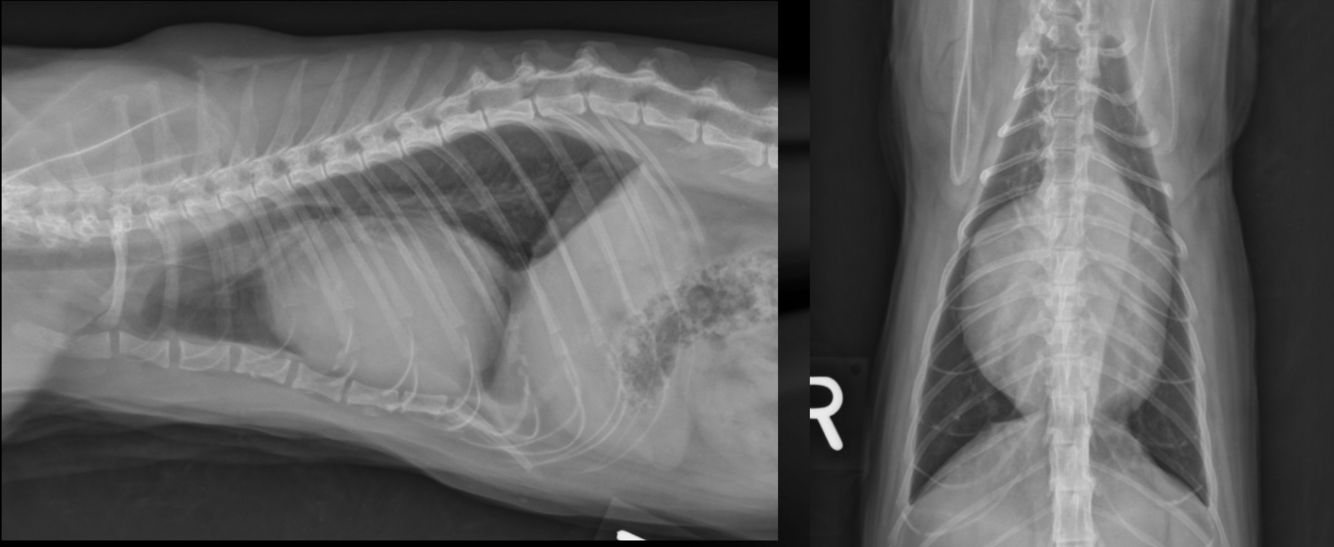

What is important regarding the ribs in these radiographs?

young dog; costal cartilages have not mineralized at all

middle-aged dog; costal cartilages have mineralized but not excessively